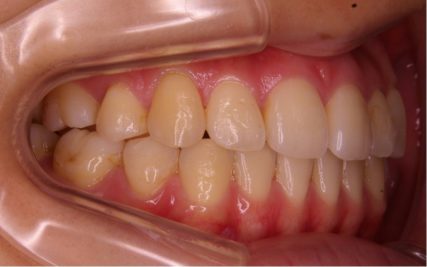

でこぼこ/20代女性

- 不正咬合/叢生(でこぼこ)

- 上下とも前歯のスペース不足が認められた。歯のサイズと顎の幅とのバランスが不調和な事が原因の1つとして考えられる。

- 上顎両側4番・上顎両側8番・下顎両側4番・下顎両側8番抜歯

- マルチブラケット装置(セルフライゲーションブラケット)/歯科矯正用アンカースクリュー

- 前歯部のでこぼこが解消され、正常咬合を獲得する事が出来た。又、歯科矯正用アンカースクリューを用いる事で抜歯スペースを有効に利用できた。